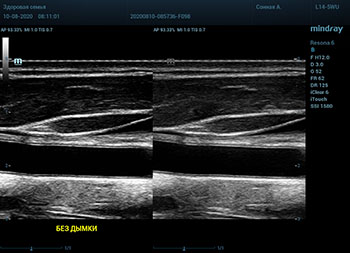

Ультразвуковое оборудование не отстает от современно тренда. В приборах серии Resona, компании Mindray, появилась новая функция постобработки изображения. Имя ей Dehaze. В переводе на наш родной язык – удаление дымки или рассеивание тумана. Инструмент позволяет корректировать интенсивность тумана или дымки. При этом сохраняется общий контраст и детализация картинки. Dehaze также позволяет проявлять детали снимка в гиперэхогенных зонах и снимать артефакты при чрезмерном усилении.

Готовый снимок или видео петля в формате DICOM несет в себе полное нативное изображение. Прибор позволяет, подобно легендарному фотошопу, удалить лишний «туман». Гиперэхогенный диффузный «засвет» изображения, из-за повышенного общего усиления, часто вредит обследованию. Однако без него некоторые вещи не видны. Показать гипоэхогенные участки и скрыть эхогенную дымку и позволяет Dehaze.